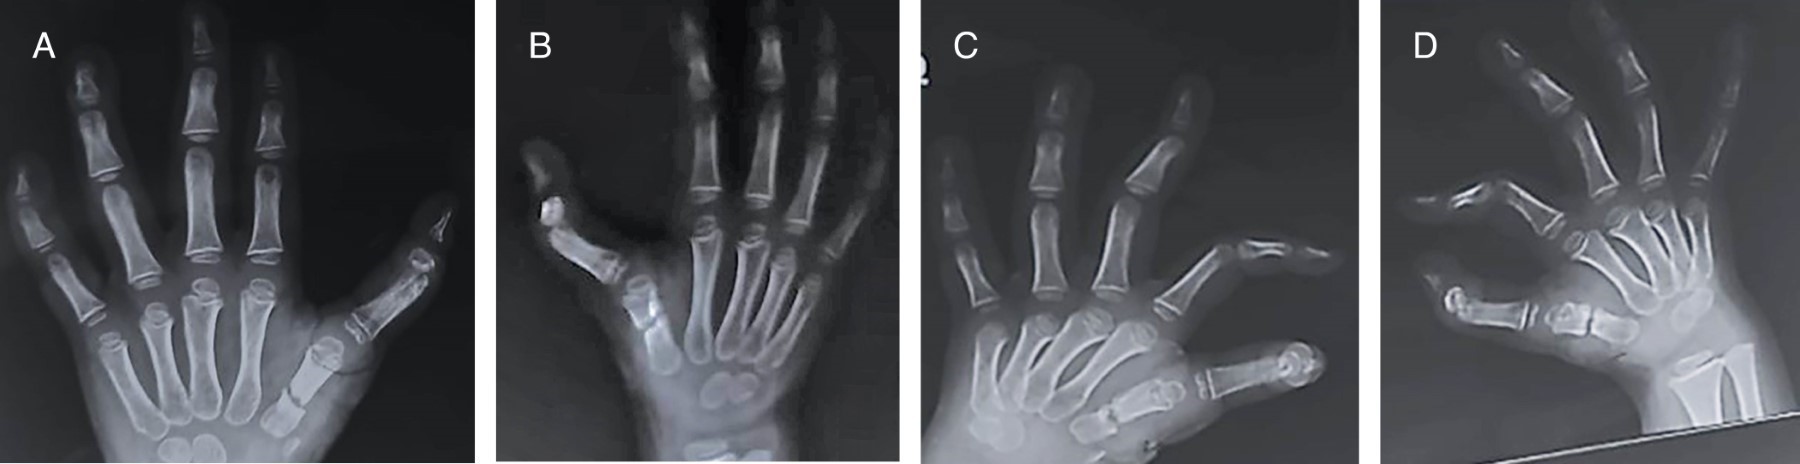

Un año después de la primera cirugía se observa presencia de pulgar trifalángico bilateral, con actitud en rotación externa de ambos pulgares con dificultar para la oposición y movimientos de pinza gruesa y fina, se solicitan radiografías dorso-palmares y oblicuas de mano observando consolidación total de ambos metacarpianos. Dos años posteriores acude a consulta de seguimiento donde se observa radiográficamente una consolidación total de primer metacarpiano bilateral, así como la presencia de una falange intermedia tipo rectangular (Figura 3), clínicamente se observa en ambas manos presencia de pulgar trifalángico, con dedo en actitud de rotación externa con dificultad para la oposición, con una longitud similar a dedo índice (Figura 4).

La paciente egresa a su domicilio, con profilaxis antibiótica a base de cefalotina y analgésicos, se mantiene vigilancia estrecha semanal en la consulta externa para valoración de heridas y llenado capilar. Se realiza valoración a las cinco semanas postquirúrgicas con nueva radiografía de control, donde se observa adecuada cicatrización de tejidos blandos, sitio de entrada de calvillos sin datos de sangrado o exudado, sin presencia de eritema (Figura 6); acude con radiografía de control donde se observan datos de consolidación ósea a nivel de primer metacarpiano, así como una fusión entre la porción proximal de f2 y la porción distal de f3 de ambos pulgares (Figura 7), clínicamente sin dolor, se retiran clavillos y se envía a rehabilitación. Un año posterior al segundo evento quirúrgico la paciente es valorada, encontrando mano derecha e izquierda con presencia de pulgar con adecuado aspecto (dos falanges, un pliegue de flexión interfalángico bien definido, lamina ungueal con crecimiento uniforme y altura del pulgar con relación a los demás dedos), en ligera rotación interna, con arcos de movilidad con adecuada abducción, extensión, flexión y oposición, presencia de pinza fina y gruesa, con adecuada fuerza muscular, sensibilidad conservada de forma bilateral (Figura 8).